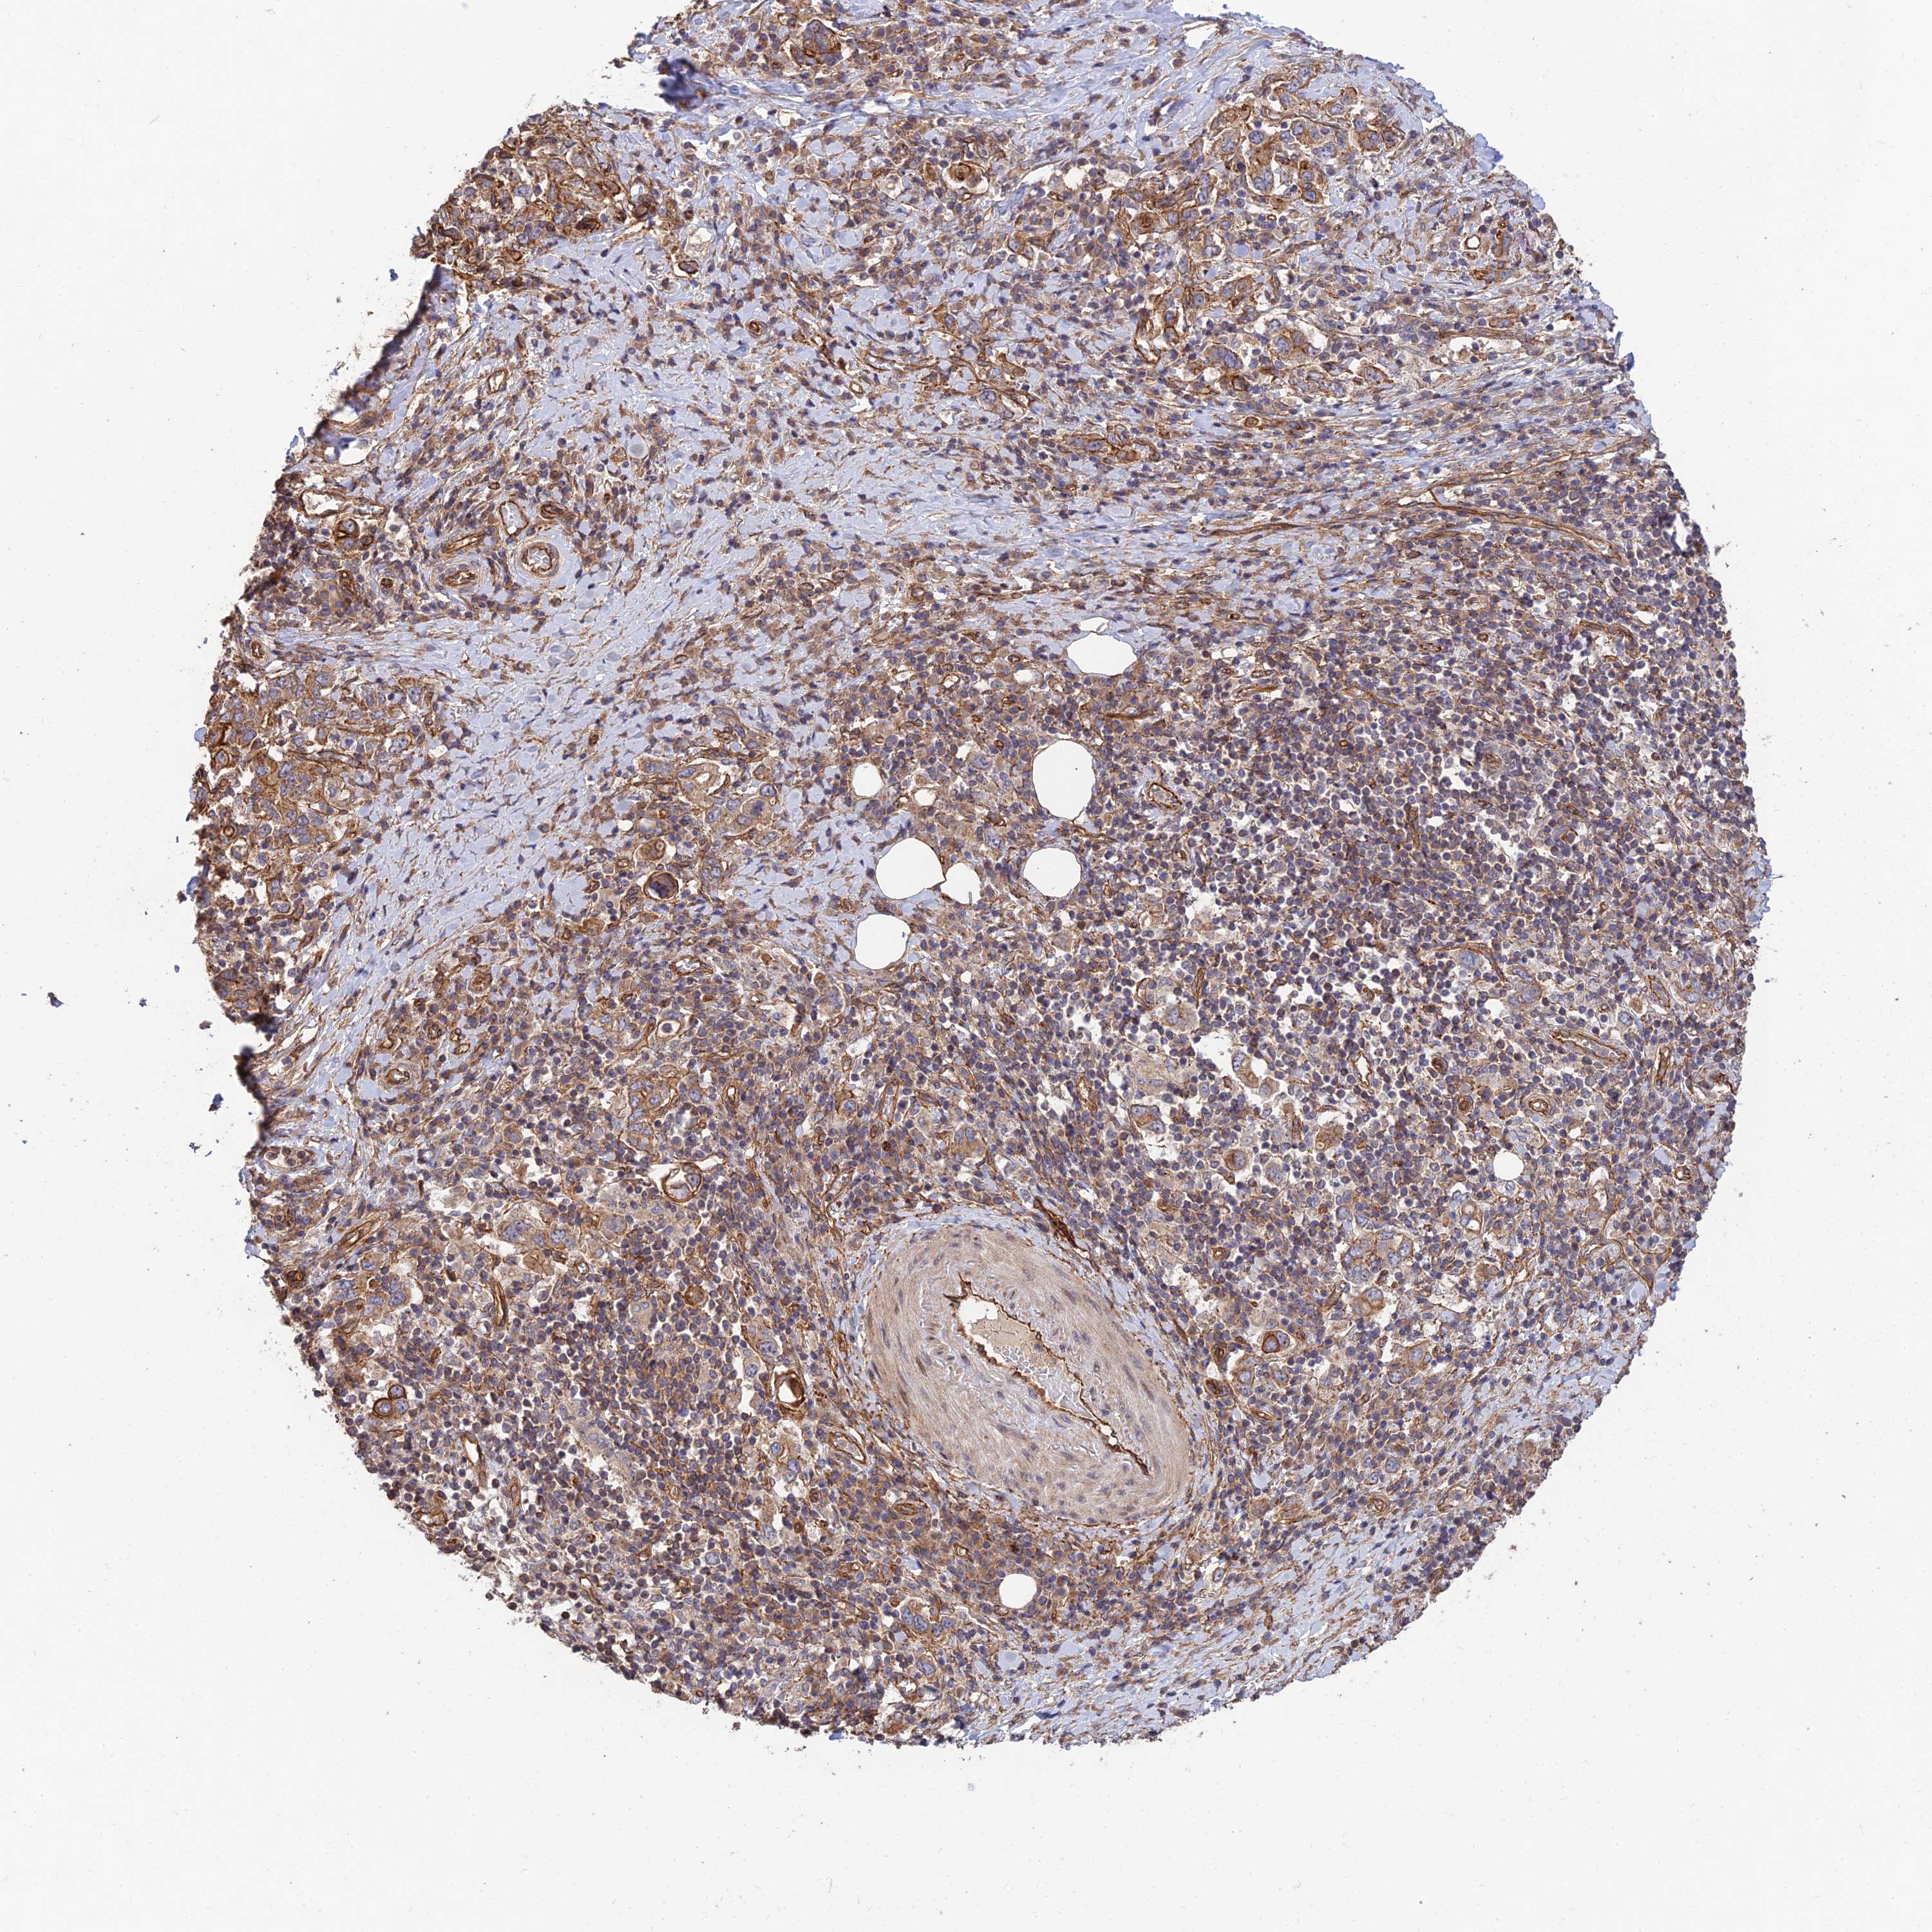

STOMACH CANCER - Protein expressioni

A mouse-over function shows sample information and annotation data. Click on an image to view it in a full screen mode. Samples can be filtered based on level of antibody staining by selecting one or several of the following categories: high, medium, low and not detected. The assay and annotation is described here.

Note that samples used for immunohistochemistry by the Human Protein Atlas do not correspond to samples in the TCGA dataset.

Antibody stainingi

Antibody staining in the annotated cell types in the current human tissue is reported as not detected, low, medium, or high, based on conventional immunohistochemistry profiling in selected tissues. This score is based on the combination of the staining intensity and fraction of stained cells.

Each image is clickable and will lead to virtual microscopy that enables deeper exploration of all samples and also displays staining intensity scores, fraction scores and subcellular localization as well as patient and tissue information for each sample.

Antibody HPA040134

Staining

High

Medium

Low

Not detected

Intensity

Strong

Moderate

Weak

Negative

Quantity

>75%

75%-25%

<25%

None

Location

Nuclear

Cytoplasmic/membranous

Cytoplasmic/membranous,nuclear

Adenocarcinoma, NOS